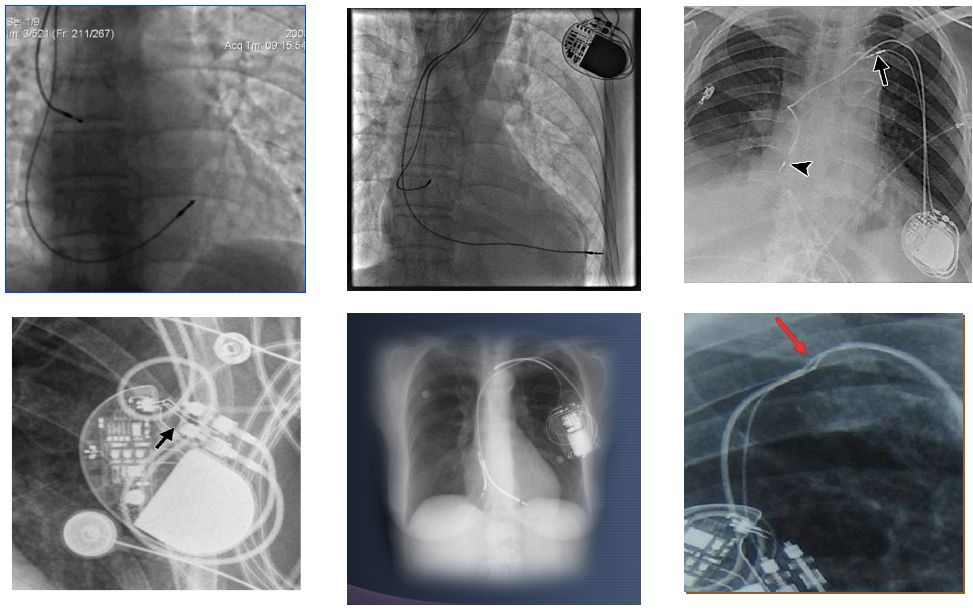

四、影像确认

X 光:脱位、穿孔、电极破裂、连接不良等;

心脏超声:穿孔,心包积液等;

为什么双极不起博起搏器故障怎么办?简单 5 步轻松搞定 | 上海心律失常论坛_https://www.jmylbn.com_新闻资讯_第13张

为什么双极不起博起搏器故障怎么办?简单 5 步轻松搞定 | 上海心律失常论坛_https://www.jmylbn.com_新闻资讯_第14张

图片来源:课件 PPT